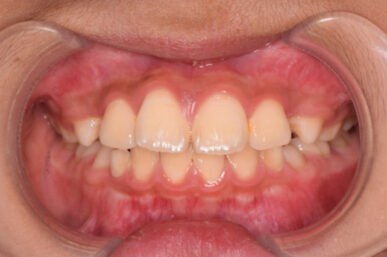

• After

治療開始が遅くてこのままでは犬歯の生えるスペースが不足していて八重歯になるところでしたが、アライナー矯正で素早く歯を動かして犬歯が生えてくるスペースを作ることで八重歯にならずに済みました。

八重歯のケースは永久歯の抜歯が必要になることもありますが、避けることができました。

矯正後は永久歯がすべて生えるまでは予防歯科で歯の生え代わりと機能を管理します。